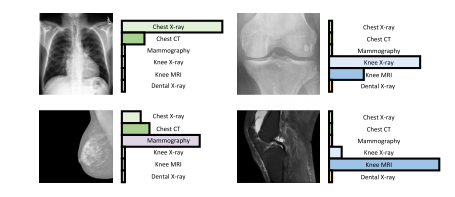

Fig. 4. Illustration of CLIP’s generalizability via domain identification.

图4:通过领域识别来展示对比语言-图像预训练模型(CLIP)通用性的图示。